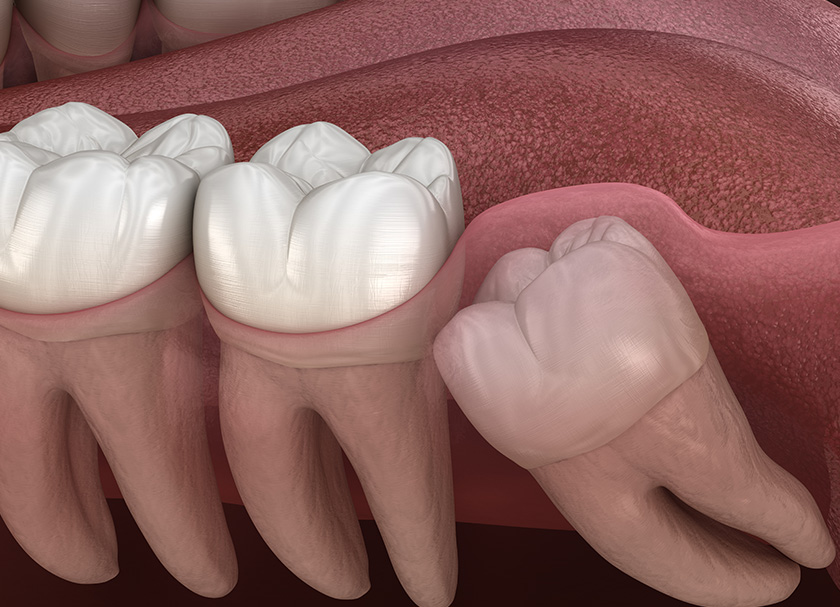

Third, molars in the rear of the mouth called impacted wisdom teeth lack sufficient space to erupt or grow correctly.

Third molars that become partially or completely wedged in the gums or jawbone are impacted wisdom teeth. This third may result in various oral health issues, such as infection, tooth decay, and gum disease. For the treatment of impacted wisdom teeth, surgery is frequently advised.

The wisdom teeth are the final set of teeth to erupt, also referred to as third molars. Between 17 and 25, they often erupt (break through your gums). Your wisdom teeth may occasionally merge with your other teeth without causing any issues. Sometimes they get caught completely or partially in your jawbone or gums. Impaction is the technical term for this. Cavities, gum disease, and infections are just a few of the dental health issues impacted wisdom teeth can bring.

The most typical kind is masticatory impaction. It happens when your wisdom teeth are pointing forward in your mouth.

The most uncommon kind of impaction, called distal impaction, occurs when your wisdom teeth are tilted toward the rear of your mouth.

When your wisdom teeth molars are in the ideal position for an eruption but are still buried behind your gums, it is said to be vertically impaction.

This condition is known as horizontal impaction when your wisdom teeth are totally on their side and buried under your gums. Because they exert excessive pressure on the teeth in front of them, wisdom teeth molars that are horizontally impacted frequently cause pain.

Impacted wisdom teeth may partially emerge such that the crown is visible, or it may never entirely emerge from the gums (fully impacted). If the tooth is completely or partially impacted, it may:

- Grow obliquely in the direction of the adjacent tooth (second molar)

- Grow at an angle at the rear of the mouth

- Wisdom teeth developed at a right angle to the neighboring teeth, as if “lying down” within the jawbone.

- Teeth stuck within the jawbone may only grow straight up or down like other teeth.